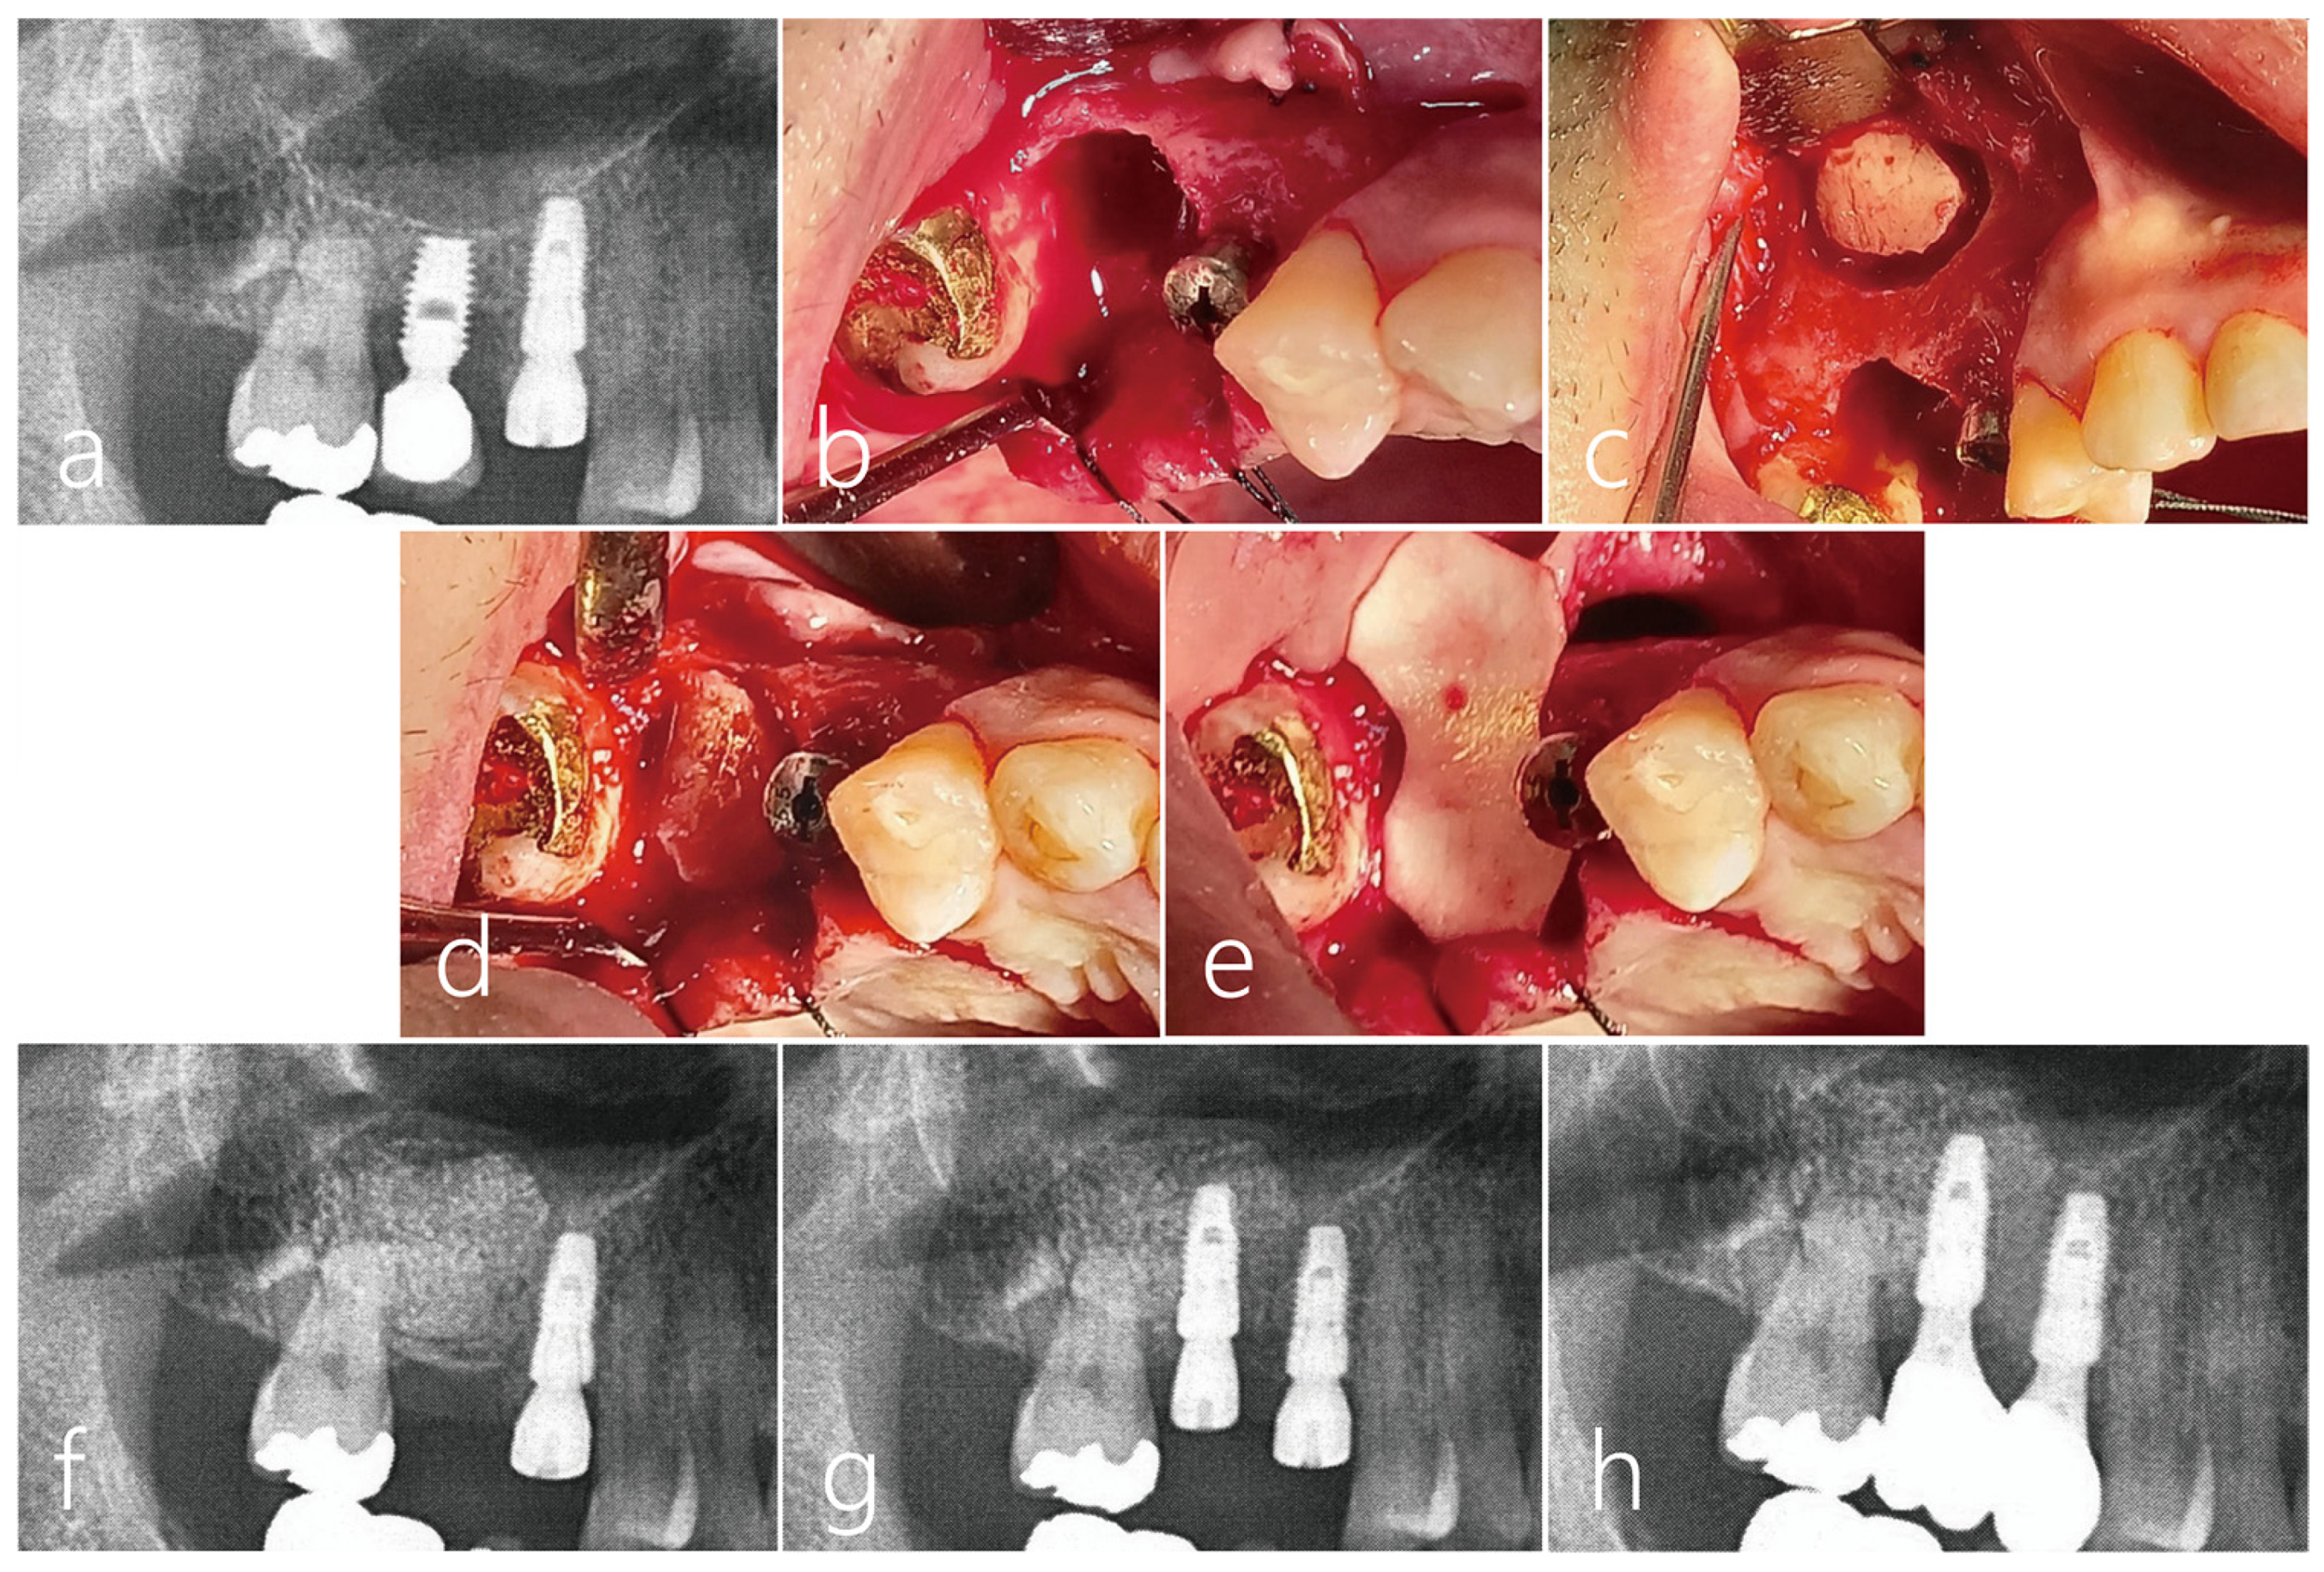

A healthy 42-year-old male non-smoker patient presented himself to the clinic for re-implantation of a #16 implant. The implant #16, which was placed 10 years ago, developed peri-implantitis with severe bone resorption and suppuration (Figure 9a). The failing implant was removed, and another implant was placed concurrently with additional transcrestal sinus floor elevation. No perforation of the sinus membrane occurred during the sinus floor elevation (Figure 9b). The removed bone from the window was used as a bone bridge for the vertical ridge augmentation of the explantation site (Figure 9c). The space between the bone bridge and the explantation defect was filled with particulate bone (Osteon III, Genoss, Suwon, Republic of Korea). The bone bridge was fixed to the adjacent native bone using the press-fit method (Figure 9d) and covered with a resorbable collagen membrane (Figure 9e). The mucoperiosteal flap was closed.

Figure 9.

Case 4 (a) The patient #16 implant had peri-implantitis with severe bone resorption; (b) For a future successful implant replacement, the failed implant was removed and a transcrestal sinus floor elevation using Summers osteotome was performed simultaneously. (c) Sinus mucosa did not perforate during sinus floor elevation; (d) The removed lateral sinus access window was used as a bone bridge for vertical ridge augmentation of the explantation site. The dead space between the bone bridge and the explantation defect was filled with particulate bone. A bone graft was also performed in the elevated sinus. Bone bridges were fixed to the adjacent crestal bone by the press-fit method; (e) The graft site was covered with a resorbable collagen membrane. The flap was closed; (f) During the healing period, there was no special event at the bone graft site of the maxillary sinus, but the wound was partially opened, and healing was somewhat delayed; (g) After 5 months, an osteotomy was performed for implant site preparation. After thoroughly removing the infiltrated soft tissue, a Ø 4.3 × 10 mm SLA-textures implant was placed. At the time of the implant placement, the existing bone bridge was well integrated with the surrounding native bone and did not move. The implant was positioned 1.0 mm subcrestally to the platform. The flap was closed with 4-0 nylon. Uncovering was performed after 4 months, and the healing process was uneventful; (h) After 2 months, the final prosthesis was placed, and after 1 year, the crestal bone level was not resorbed, and chewing function was restored.

During the healing period, there were no adverse events at the bone graft site, but the wound was partially opened, and healing was delayed (Figure 9f). After 5 months, the mucoperiosteal flaps were reflected for implant placement. The bone bridge seemed to have resorbed slightly and soft tissue ingrowth was observed. However, the existing bone bridge was well integrated with the surrounding native bone and did not show any mobility. An osteotomy was prepared for a Ø 4.3 × 10 mm SLA-textures implant (Implantium, Dentium, Suwon, Republic of Korea), and the fixture was placed with good initial stability. The implant was positioned 1.0 mm subcrestally to the platform, and the healing abutment was inserted. (Figure 9g). The flap was closed with 4-0 nylon. Uncovering was performed after 4 months, and the healing process was uneventful. After 2 months, the final prosthesis was delivered. One year after the prosthesis was delivered, no resorption was observed in the crestal bone level, and chewing function was restored (Figure 9h) (Table 1).